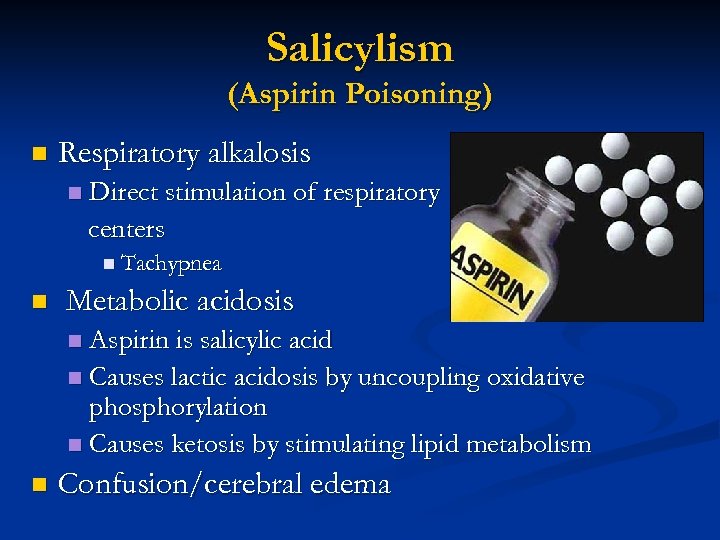

Salicylism (Aspirin Poisoning) n Respiratory alkalosis n Direct stimulation of respiratory centers n Tachypnea n Metabolic acidosis Aspirin is salicylic acid n Causes lactic acidosis by uncoupling oxidative phosphorylation n Causes ketosis by stimulating lipid metabolism n n Confusion/cerebral edema

Salicylism (Aspirin Poisoning) n Respiratory alkalosis n Direct stimulation of respiratory centers n Tachypnea n Metabolic acidosis Aspirin is salicylic acid n Causes lactic acidosis by uncoupling oxidative phosphorylation n Causes ketosis by stimulating lipid metabolism n n Confusion/cerebral edema